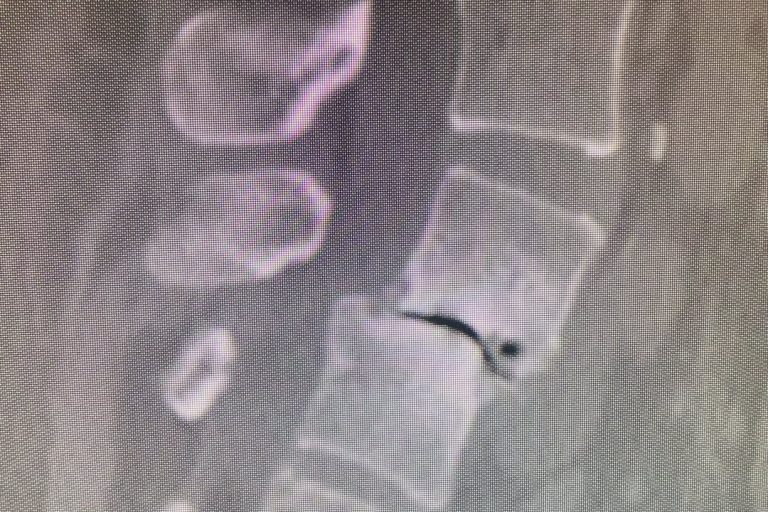

Cervical total disc replacement or disc arthroplasty is becoming an increasingly popular procedure. Now, the cervical disc replacements are even approved for doing 2 levels, as in this recent case that I performed. Is it right for you? Many things are possible in spine surgery but only a few things are most appropriate for you…